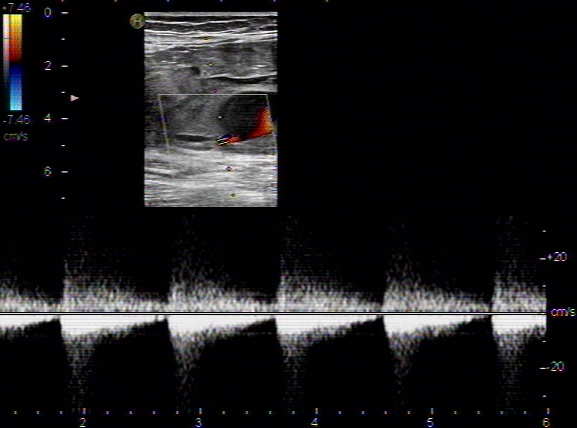

可見雙腔血流,圖中藍(lán)色血流為逆向血流提示假腔。腹主動(dòng)脈長(zhǎng)軸切面,腔內(nèi)可見膜樣強(qiáng)回聲,呈雙腔征。